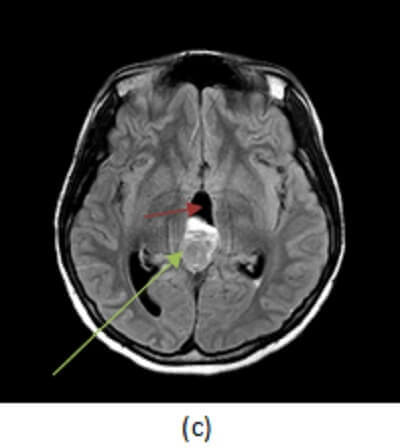

Figure 1: axial T2 (a, red arrow) and FLAIR (b, blue arrow) sequences demonstrate a large lobulated pineal mass with ill defined borders and heterogenous signal. (c, green arrow) post contrast T1 demonstrates heterogenous enhancement to the mass. There is hydrocephalus, manifested by an enlarged third ventricle (purple arrow).

Pineoblastomas are highly malignant tumors of early childhood, more common in females with peak incidence of 3 years of age. Pineoblastomas are typically large, solid, lobulated masses that compress or infiltrate adjacent structures, that seed the meninges and that may have drop metastasize in the spine. They are heterogenous masses, hyperdense on CT and iso/hypo dense on T2. They enhance heterogeneously and demonstrate restricted diffusion due to high tumor cellularity. Treatment includes surgical resection and radiation of the entire neuraxias (due to the high frequency of metasatasis at presentation).